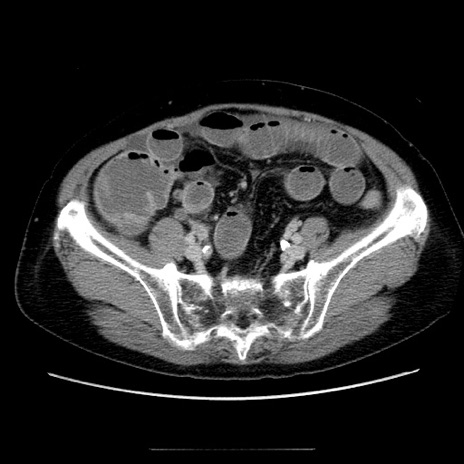

症例5(横断像)

【症例】70歳代女性

【主訴】お腹が張る

【現病歴】1週間くらい前から腹部膨満の自覚あり。昨日夜から増悪したため、本日救急外来受診。

【身体所見】意識清明、BT 36.5℃、BP 165/106mmHg、HR 80bpm、SpO2 98%、腹部:膨満、軟、自発痛・圧痛なし、触診にて不快感あり、腸蠕動音:減弱

【データ】WBC 12600、CRP 1.04